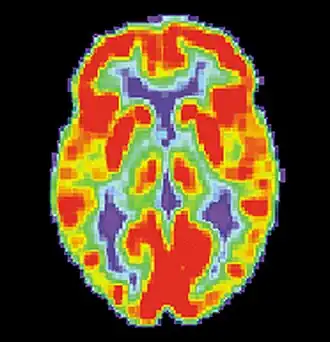

A tomografia por emissão de pósitrons (PET) cerebral com 18F-fluorodeoxiglicose (18F-FDG) pode mostrar uma região do cérebro com metabolismo de glicose diminuído no intervalo entre as crises; essa região hipometabólica pode corresponder ao foco da crise, e a PET é mais sensível para a localização do foco da crise no lobo temporal em comparação com a epilepsia proveniente de outros lobos cerebrais.[4] A tomografia computadorizada por emissão de fóton único (SPECT) pode mostrar uma região de fluxo sanguíneo reduzido que ocorre 40 a 60 segundos após a injeção durante a convulsão; essa região de fluxo sanguíneo reduzido pode corresponder ao foco da convulsão.[4]